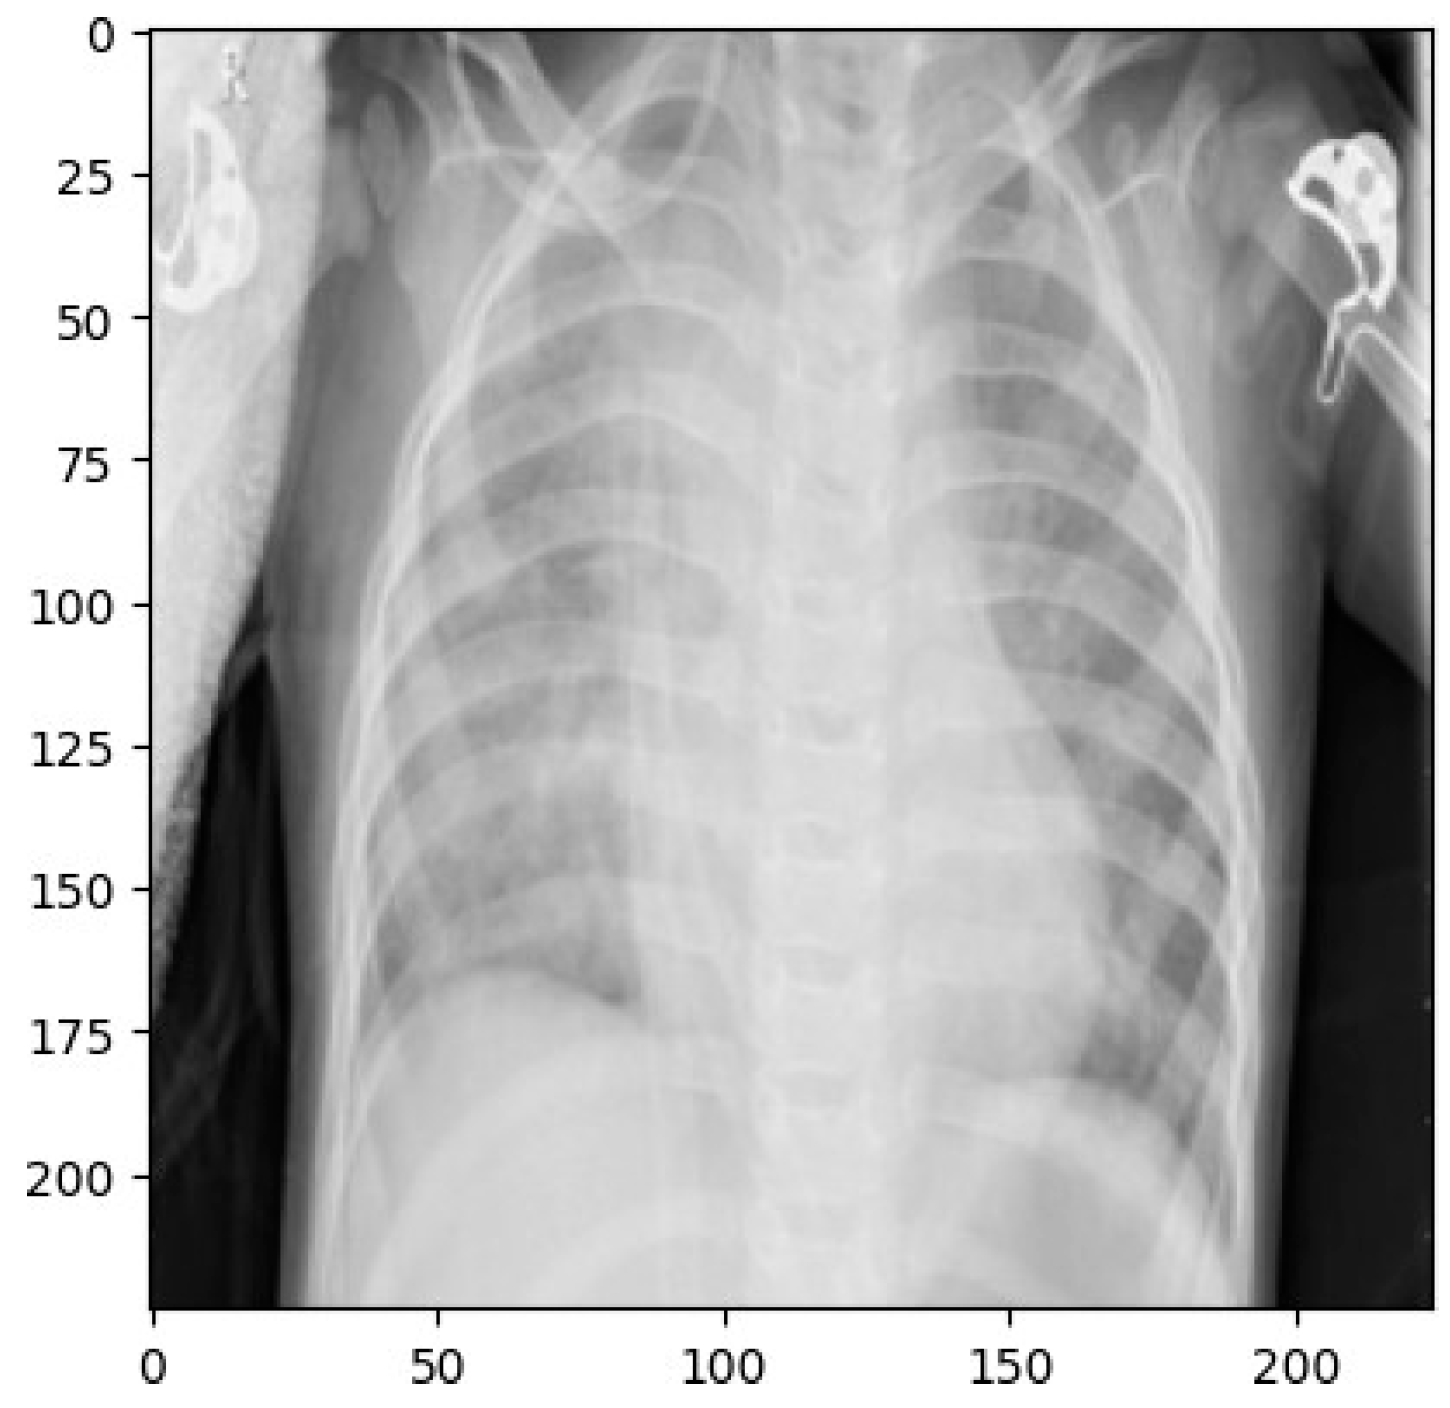

2.4. Image Enhancement Techniques

Resizing